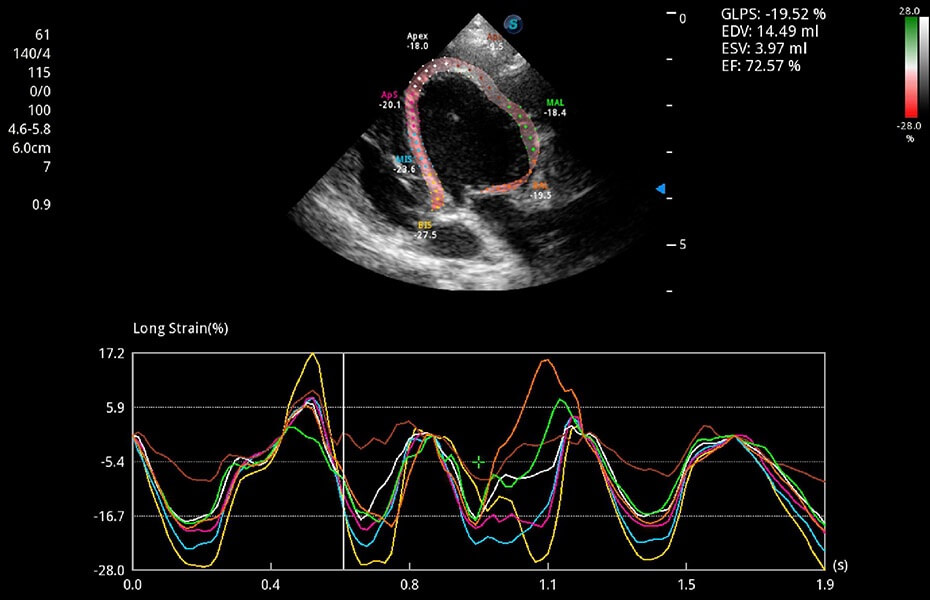

ProPet 60 作為一款高端臺式動物超聲設(shè)備,為動物醫(yī)生的日常診斷提供了一系列貼合動物臨床需求、解決臨床實(shí)際問題的高級成像功能。憑借全系列高清探頭,滿足醫(yī)生對腹部、心臟、生殖、淺表、肌骨等成像的所有需求,切實(shí)幫助您提升檢查效率,提高診斷信心。